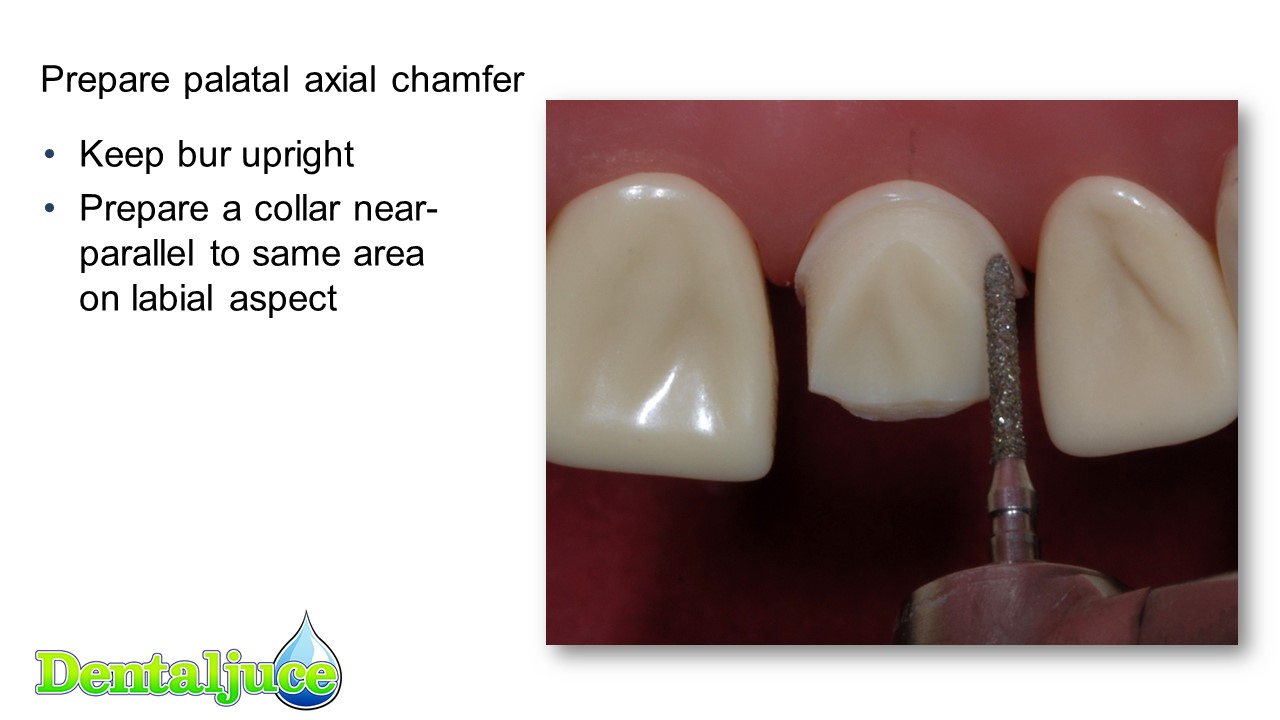

Incisor MC (PFM) Prep | Enhanced Dental CPD Online

www.dentaljuce.com

www.dentaljuce.com

Incisor MC (PFM) Prep | Enhanced Dental CPD Online

www.dentaljuce.com

www.dentaljuce.com